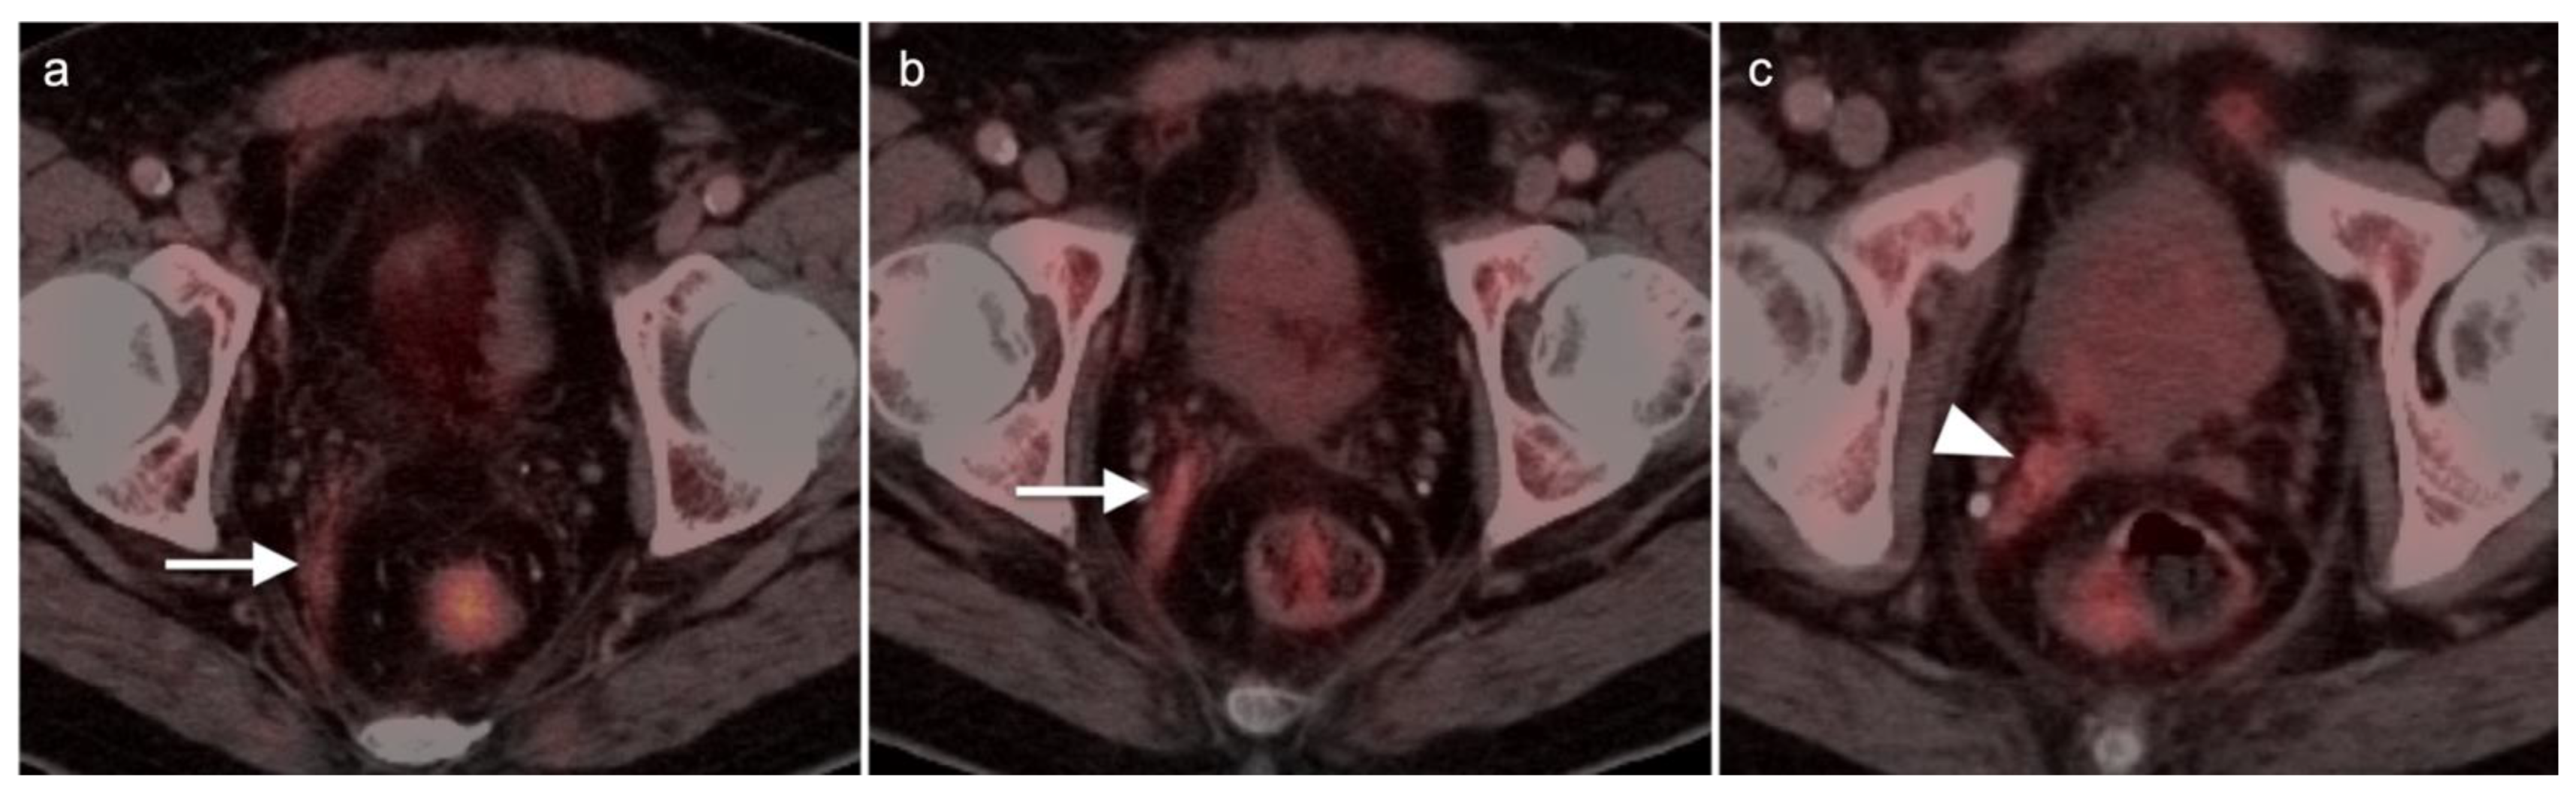

3.1. Prostate Cancer

3.2. Urothelial Carcinoma